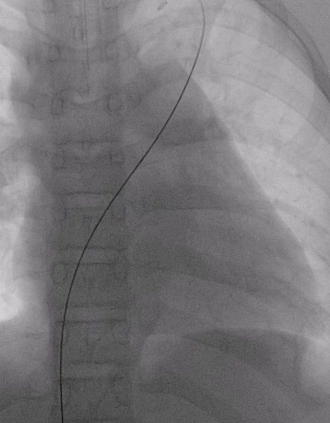

建立输送轨道

飘导丝法导丝过室间隔缺损

圈套器抓捕导丝

送入8F输送鞘

改变输送鞘方向

使输送鞘朝向心尖